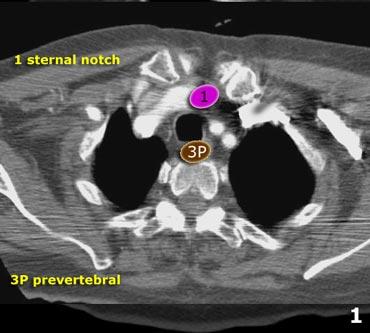

3P.Trước cột sống

Các hạch không tiếp giáp với khí quản như các hạch ở nhóm 2, mà nằm sau thực quản, tức là ở vị trí trước cột sống.

- Hạch bạch huyết khuyết ức có thể quan sát thấy ở mức này và phía trên mức này

- Trước mạch máu và Sau khí quản: nằm trước các mạch máu (3A) hoặc trước cột sống (3P)